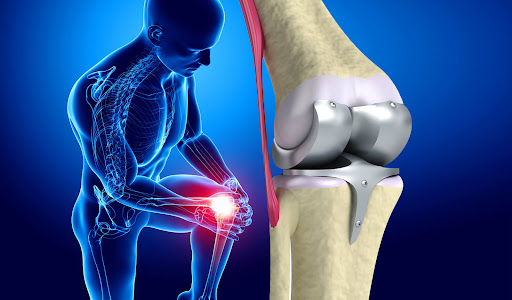

نوبتدهی ام آر آی زانو

تصویربرداری

1404/11/19

ام آر آی زانو چیست و چه مزایایی دارد؟ ام آر آی زانو یکی از دقیق ترین روش های تصویربرداری پزشکی است که با استفاده از *...